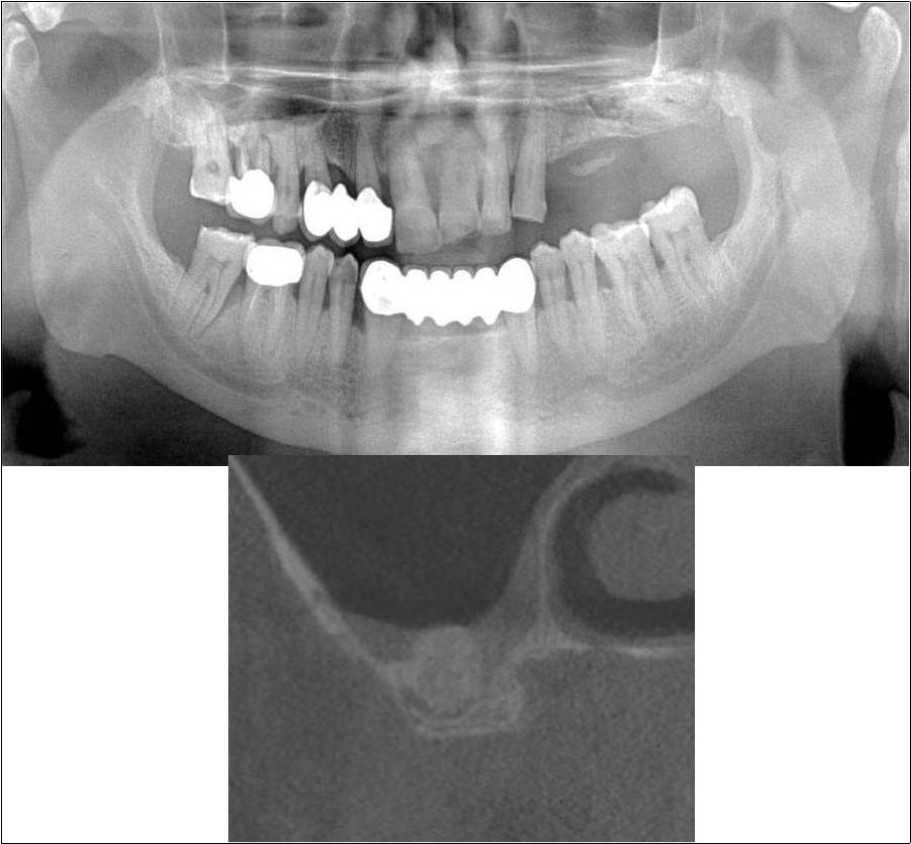

Case Report 2:

A 42 years old male patient reported to the Department of Oral and Maxillofacial Surgery, D.A.P.M.R.V Dental College and Hospital with a chief complaint of inability to chew food because of missing teeth in upper right and left back tooth regions from past one year. The teeth were extracted an year ago because of gross loss of tooth structure and poor prognosis for root canal treatment. Patient was a hypertensive since 4 years and was on medication for the same. Patient did not give history of any existing sinus pathologies. All possible rehabilitative options were explained to the patient and a treatment plan of replacement of missing teeth with implant supported prosthesis using one dental implant in 17 region was finalized.

Clinical and Radiological Assessment:

1.Partially edentulous maxillary and mandibular arches with missing 17, 26, 45, 46;

2.Increased pneumatisation of right maxillary sinus;

3.Height of available bone- 6.6mm;

4.Transverse thickness of available bone (CBCT evaluation)- 11mm;

5.Inter-ridge space adequate to place implant (10mm).

Treatment:

Patient underwent the procedure of indirect sinus elevation using sinus osteotomes in relation to 17 region. Calcium phosphosilicate putty was dispensed as the graft material through the crestal osteotomy site to maintain the elevated sinus membrane followed by placement of a dental implant measuring 5 x 10mm under local anaesthesia and strict aseptic protocols .The implant was allowed to osseo-integrate for a period of six months during which the patient was followed-up periodically and was assessed for peri-implantitis, crestal bone loss and mobility. At the end of 6 months, a repeat CBCT scan was advised to evaluate the increase in bone height. (Figure 9a,b, pre-treatment; Figure 10a,b, post-treatment)

Figure 9.(a,b) Pre-treatment OPG and cross section of CBCT showing residual alveolar bone height for Case No.2

Figure 10.(a,b) Post-treatment OPG and cross section of CBCT showing residual alveolar bone height for Case No.2

Case Report 3:

A 75 years old male patient reported to the Department of Oral and Maxillofacial Surgery, D.A.P.M.R.V Dental College and Hospital seeking options for replacement of his missing tooth in right upper back tooth region with a fixed prosthesis. The tooth was extracted around 10 years ago because of pain and infection associated with the tooth. No prosthetic rehabilitation was carried-out in the past. 16 was found to be missing and the patient reported that healing was uneventful post-extraction of the tooth. The patient was a controlled diabetic and hypertensive and was on medications for the same. Patient did not give history of any existing sinus pathologies. All possible rehabilitative options were explained to the patient and a treatment plan of replacement of missing 16 with implant supported prosthesis using one dental implant was finalized

Clinical and Radiological Assessment:

1.Partially edentulous maxillary arch with missing 16;

2.Increased pneumatisation of right maxillary sinus;

3.Height of available bone- 5.3mm;

4.Transverse thickness of available bone (CBCT evaluation)- 10.2mm;

5.Inter-ridge space adequate to place implant (10mm).

Treatment:

Patient underwent the procedure of indirect sinus elevation using sinus osteotomes in relation to 16 region. Calcium phosphosilicate putty was dispensed as the graft material through the crestal osteotomy site to maintain the elevated sinus membrane followed by placement of a dental implant measuring 5 x 10mm under local anaesthesia and strict aseptic protocols. The implant was allowed to osseo-integrate for a period of six months during which the patient was followed-up periodically and was assessed for peri-implantitis, crestal bone loss and mobility. At the end of 6 months, a repeat CBCT scan was advised to evaluate the increase in bone height. (Figure 11a,b, pre-treatment; Figure 12a,b, post-treatment)

Figure 11.(a,b) Pre-treatment OPG and cross section of CBCT showing residual alveolar bone height for Case No.3

Figure 12.(a,b) Post-treatment OPG and cross section of CBCT showing residual alveolar bone height for Case No.3;